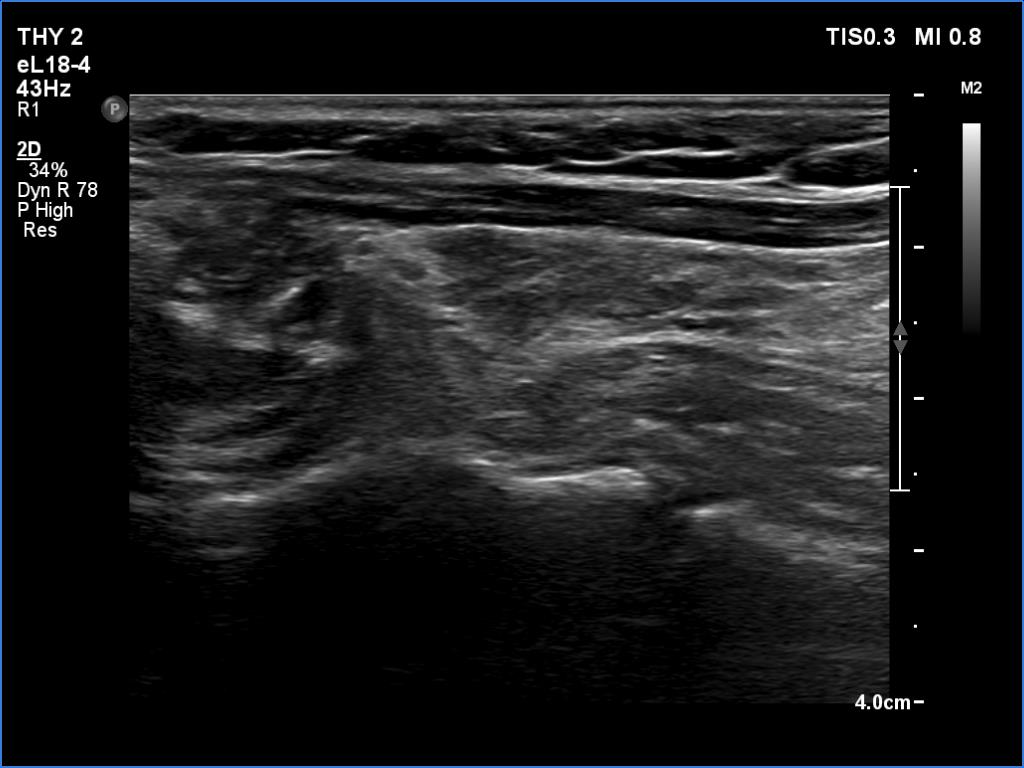

Elastography - case 650 (ultrasonographic picture 7)

Left lobe, longitudinal view.